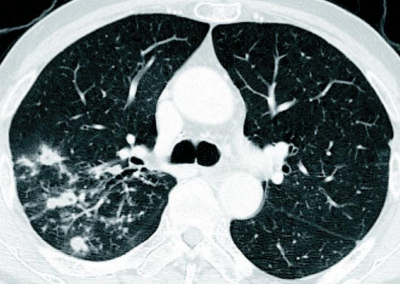

71 歳の男性。血痰を主訴に来院した。2か月前から微熱があり、2週前から断続的に血痰の排出が続いている。かかりつけ医で糖尿病の内服加療中であるが、コントロールは良くないと言われているという。呼吸音は両側胸部に coarse cracklesを聴取する。胸部エックス線写真及び胸部造影 CTを別に示す。

亜急性の経過、血痰、画像所見、糖尿病による易感染により肺結核の可能性を考える必要あり。